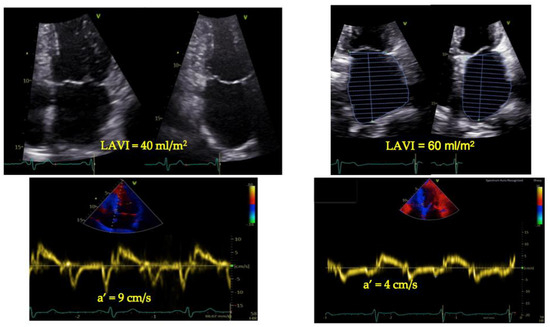

5. Tissue Doppler Imaging and LA Function: A Simplified, Complementary Approach

6. TDI-a’ and Outcome

7. TDI-a’ Integrated Echocardiographic Indices